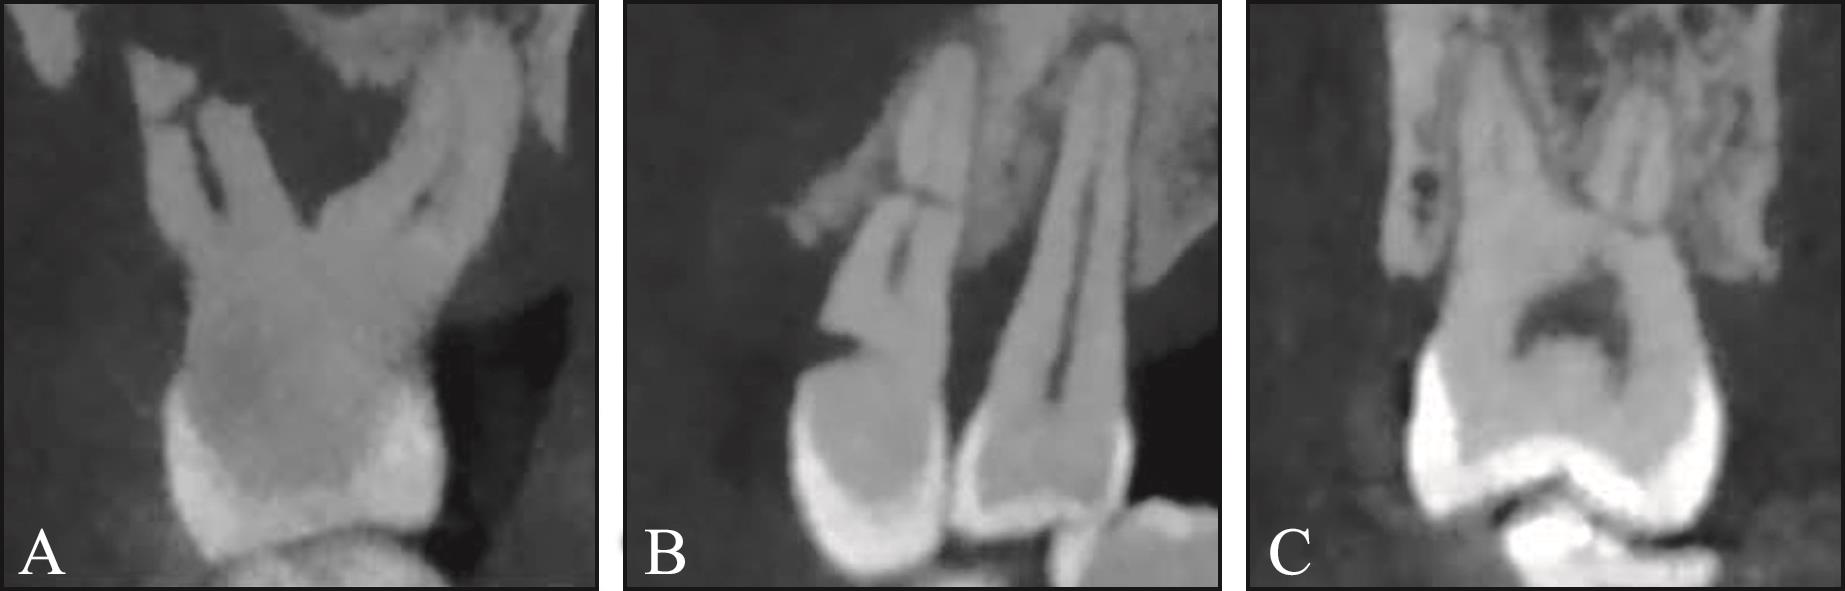

目的 探究根管治疗与非根管治疗根折后牙的临床及锥形束CT(CBCT)特征是否存在差异。 方法 回顾性收集CBCT检查发现的305例患者的340颗根折后牙,根据根折牙是否行根管治疗分为根管治疗牙和非根管治疗牙。记录根折患者的年龄和性别,在CBCT图像上评估根折发生的牙位、牙根位、根折类型(纵折、横折、斜折、不规则折)、牙根纵折方向、横折线位置及根折线周围骨吸收情况。 结果 1)非根管治疗与根管治疗根折的牙位差异有统计学意义(P=0.028)。二者根折的牙位均以上颌磨牙和下颌磨牙为主,但根管治疗牙前磨牙的发生比例(27.2%)高于非根管治疗牙(14.2%)。2)非根管治疗与根管治疗根折的牙根位差异有统计学意义(P=0.037),最常见牙根位均是下颌磨牙近中根(发生率分别为36.4%、32.2%),但排名第二的牙根位分别是上颌磨牙腭根(23.0%)、上颌前磨牙牙根(20.3%)。3)非根管治疗与根管治疗根折牙折裂类型的差异有统计学意义(P<0.001)。非根管治疗牙纵折占比为43.6%,而根管治疗牙纵折占比高达75.6%。4)非根管治疗与根管治疗纵折牙根纵折方向的差异无统计学意义(P=0.58),均以颊舌向为主(86.0%、84.1%)。5)非根管治疗与根管治疗牙横折发生位置的差异无统计学意义(P=0.132),均以根颈1/3区最常见。6)非根管治疗与根管治疗根折折裂线周围骨吸收的差异有统计学意义(P<0.001)。59.0%的非根管治疗根折牙折裂线周围有骨吸收,而根管治疗根折牙中91.8%折裂线周围有骨吸收。 结论 非根管治疗与根管治疗根折牙在临床和CBCT特征上均存在差异,非根管治疗根折牙更加复杂多变的特征表明复杂的咬合因素在根折发生中所起的作用,而根管治疗根折牙更高的一致性表明其根折发生可能与根管治疗对牙齿的结构改变有关。

Objective This study aimed to investigate the clinical and cone beam computed tomography (CBCT) characteristics of root fractures in endodontically versus nonendodontically treated posterior teeth. Methods A total of 340 posterior teeth from 305 patients were retrospectively collected. The fractured teeth were divided into endodontically treated (ET) teeth and nonendodontically treated (NET) teeth. The clinical information (age and gender of patients) was recorded. The type of fractured tooth, fractured root, orientation of fracture lines (vertical, horizontal, oblique, and irregular), direction of vertical fracture lines, location of horizontal root fractures, and bone resorption around fractured roots were evaluated and recorded based on CBCT images. Results 1) The distribution of teeth was significantly different between NET and ET teeth (P=0.028). Root fractures predominantly occurred in mandibular and maxillary molars. However, the proportion of premolars was significantly higher in ET teeth (27.2%) than in NET teeth (14.2%). 2) We observed a significant difference in root distribution between NET roots and ET roots (P=0.037). The mesial roots of mandibular molars were the most common fractured roots in NET and ET roots (36.4% in NET roots and 32.2% in ET roots); however, the second most common roots were the palatal roots of maxillary molars in NET roots (23.0%) and the maxillary premolar roots in ET roots (20.3%). 3) A statistically significant difference in the orientation of root fractures was observed between the two groups (P<0.001). Vertical root fractures accounted for only 43.6% of all root fractures in NET root fractures, whereas they accounted for 75.6% in ET root fractures. 4) For vertical root fractures, the direction of fracture lines between NET and ET root fractures was not significantly different (P=0.58), with both types predominantly presenting as buccal-palatal fractures (86.0% and 84.1%). 5) No significant difference was observed in the location of horizontal fractures between NET and ET root fractures (P=0.132), and the most common site was the cervical third of roots. 6) Bone loss around fractured lines significantly differed between NET and ET root fractures (P<0.001). Around 59% exhibited obvious bone loss around fractured roots in NET root fractures, whereas 91.8% of fractured roots presented bone loss in ET root fractures. Conclusion The NET root fractured teeth and ET root fractured teeth presented quite different clinical and CBCT characteristics. The complex and diverse traits of NET root fractured teeth indicate the influence of multifaceted occlusal factors in their occurrence. By contrast, ET root fractured teeth demonstrate high uniformity, indicating that their occurrence may be related to the structural changes caused by endodontic treatment.